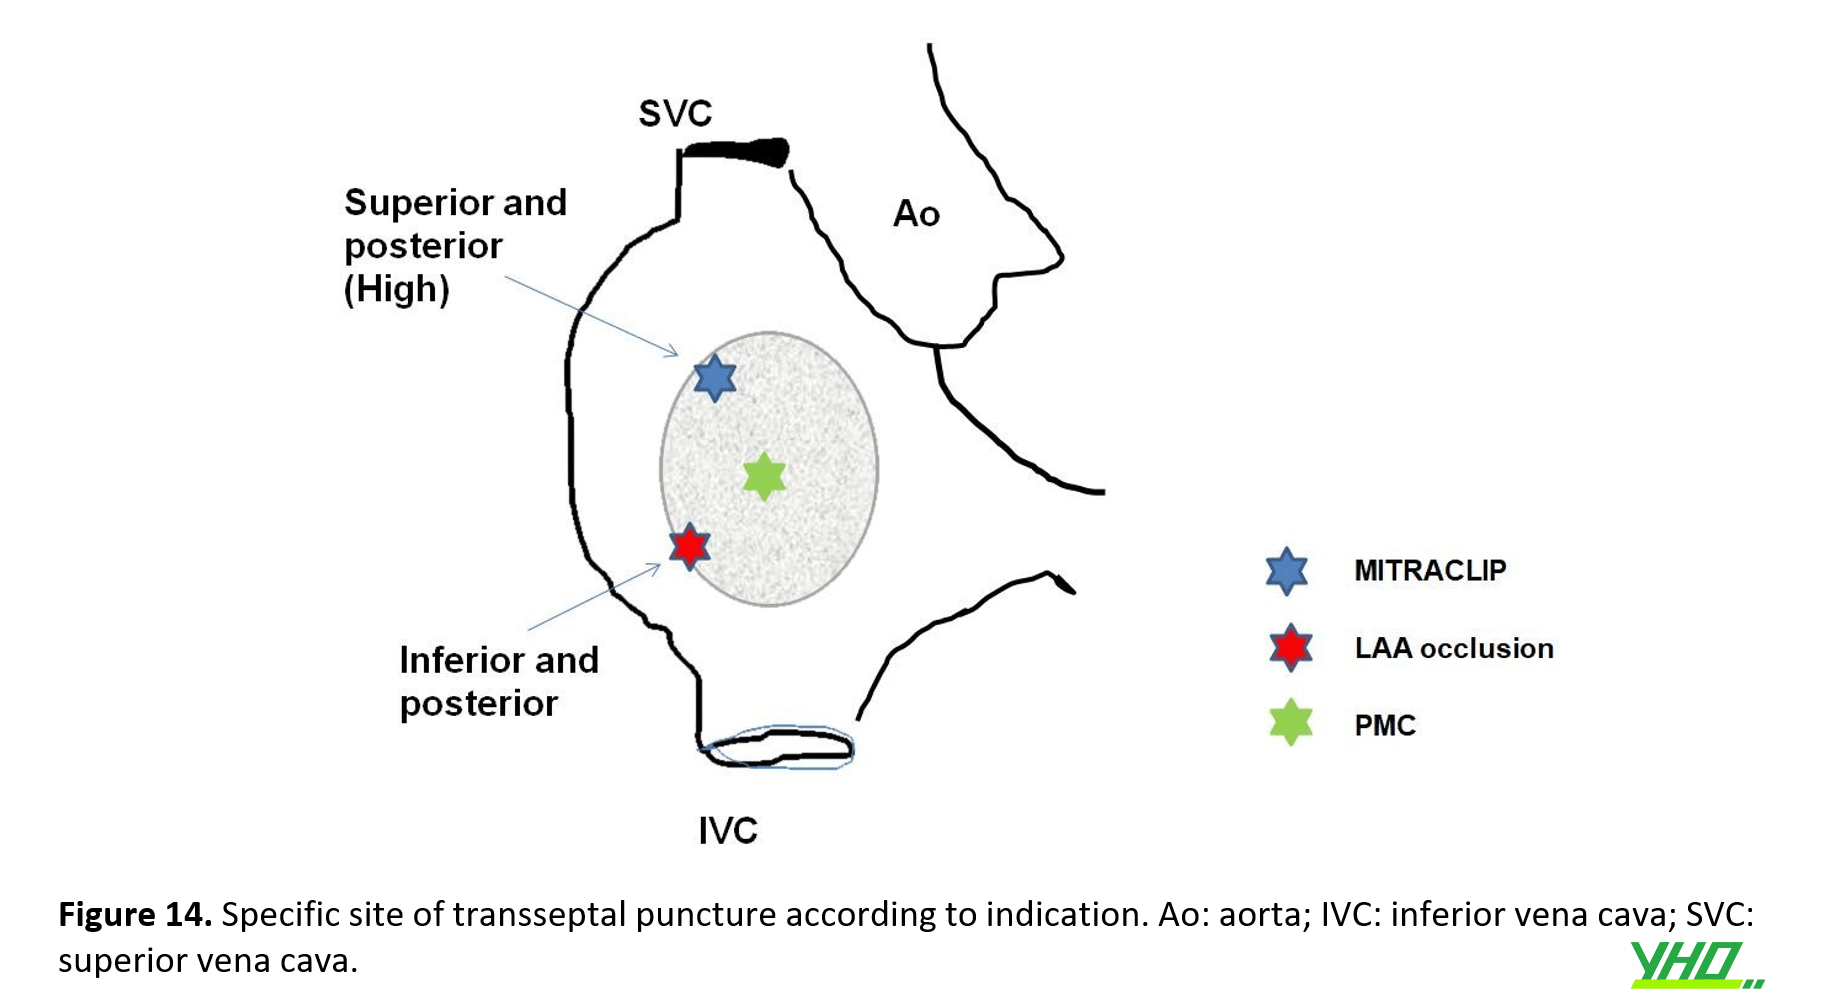

Đây cũng là công nghệ duy nhất hiện nay cho phép chọc xuyên vách liên nhĩ ở một vị trí rất cụ thể như được yêu cầu trong nhiều loại thủ thuật can thiệp (hình 14)

Nếu việc chọc txuyên vách liên nhĩ được hướng dẫn bởi TOE ba mặt cắt thì TOE từng mặt cắt được sử dụng tuần tự để xác định chính xác vị trí chọc thủng ưa thích: (1) chế độ xem trục dài ở 90−120°, cho phép định hướng trên dưới; (2) chế độ xem trục ngắn ở góc (30−50°), cho phép định hướng trước sau; (3) mặt cắt bốn buồng (0°), được sử dụng để xác định chiều cao chính xác phía trên van hai lá, là bắt buộc khi thực hiện MitraClip và các thủ thuật van hai lá qua da khác.